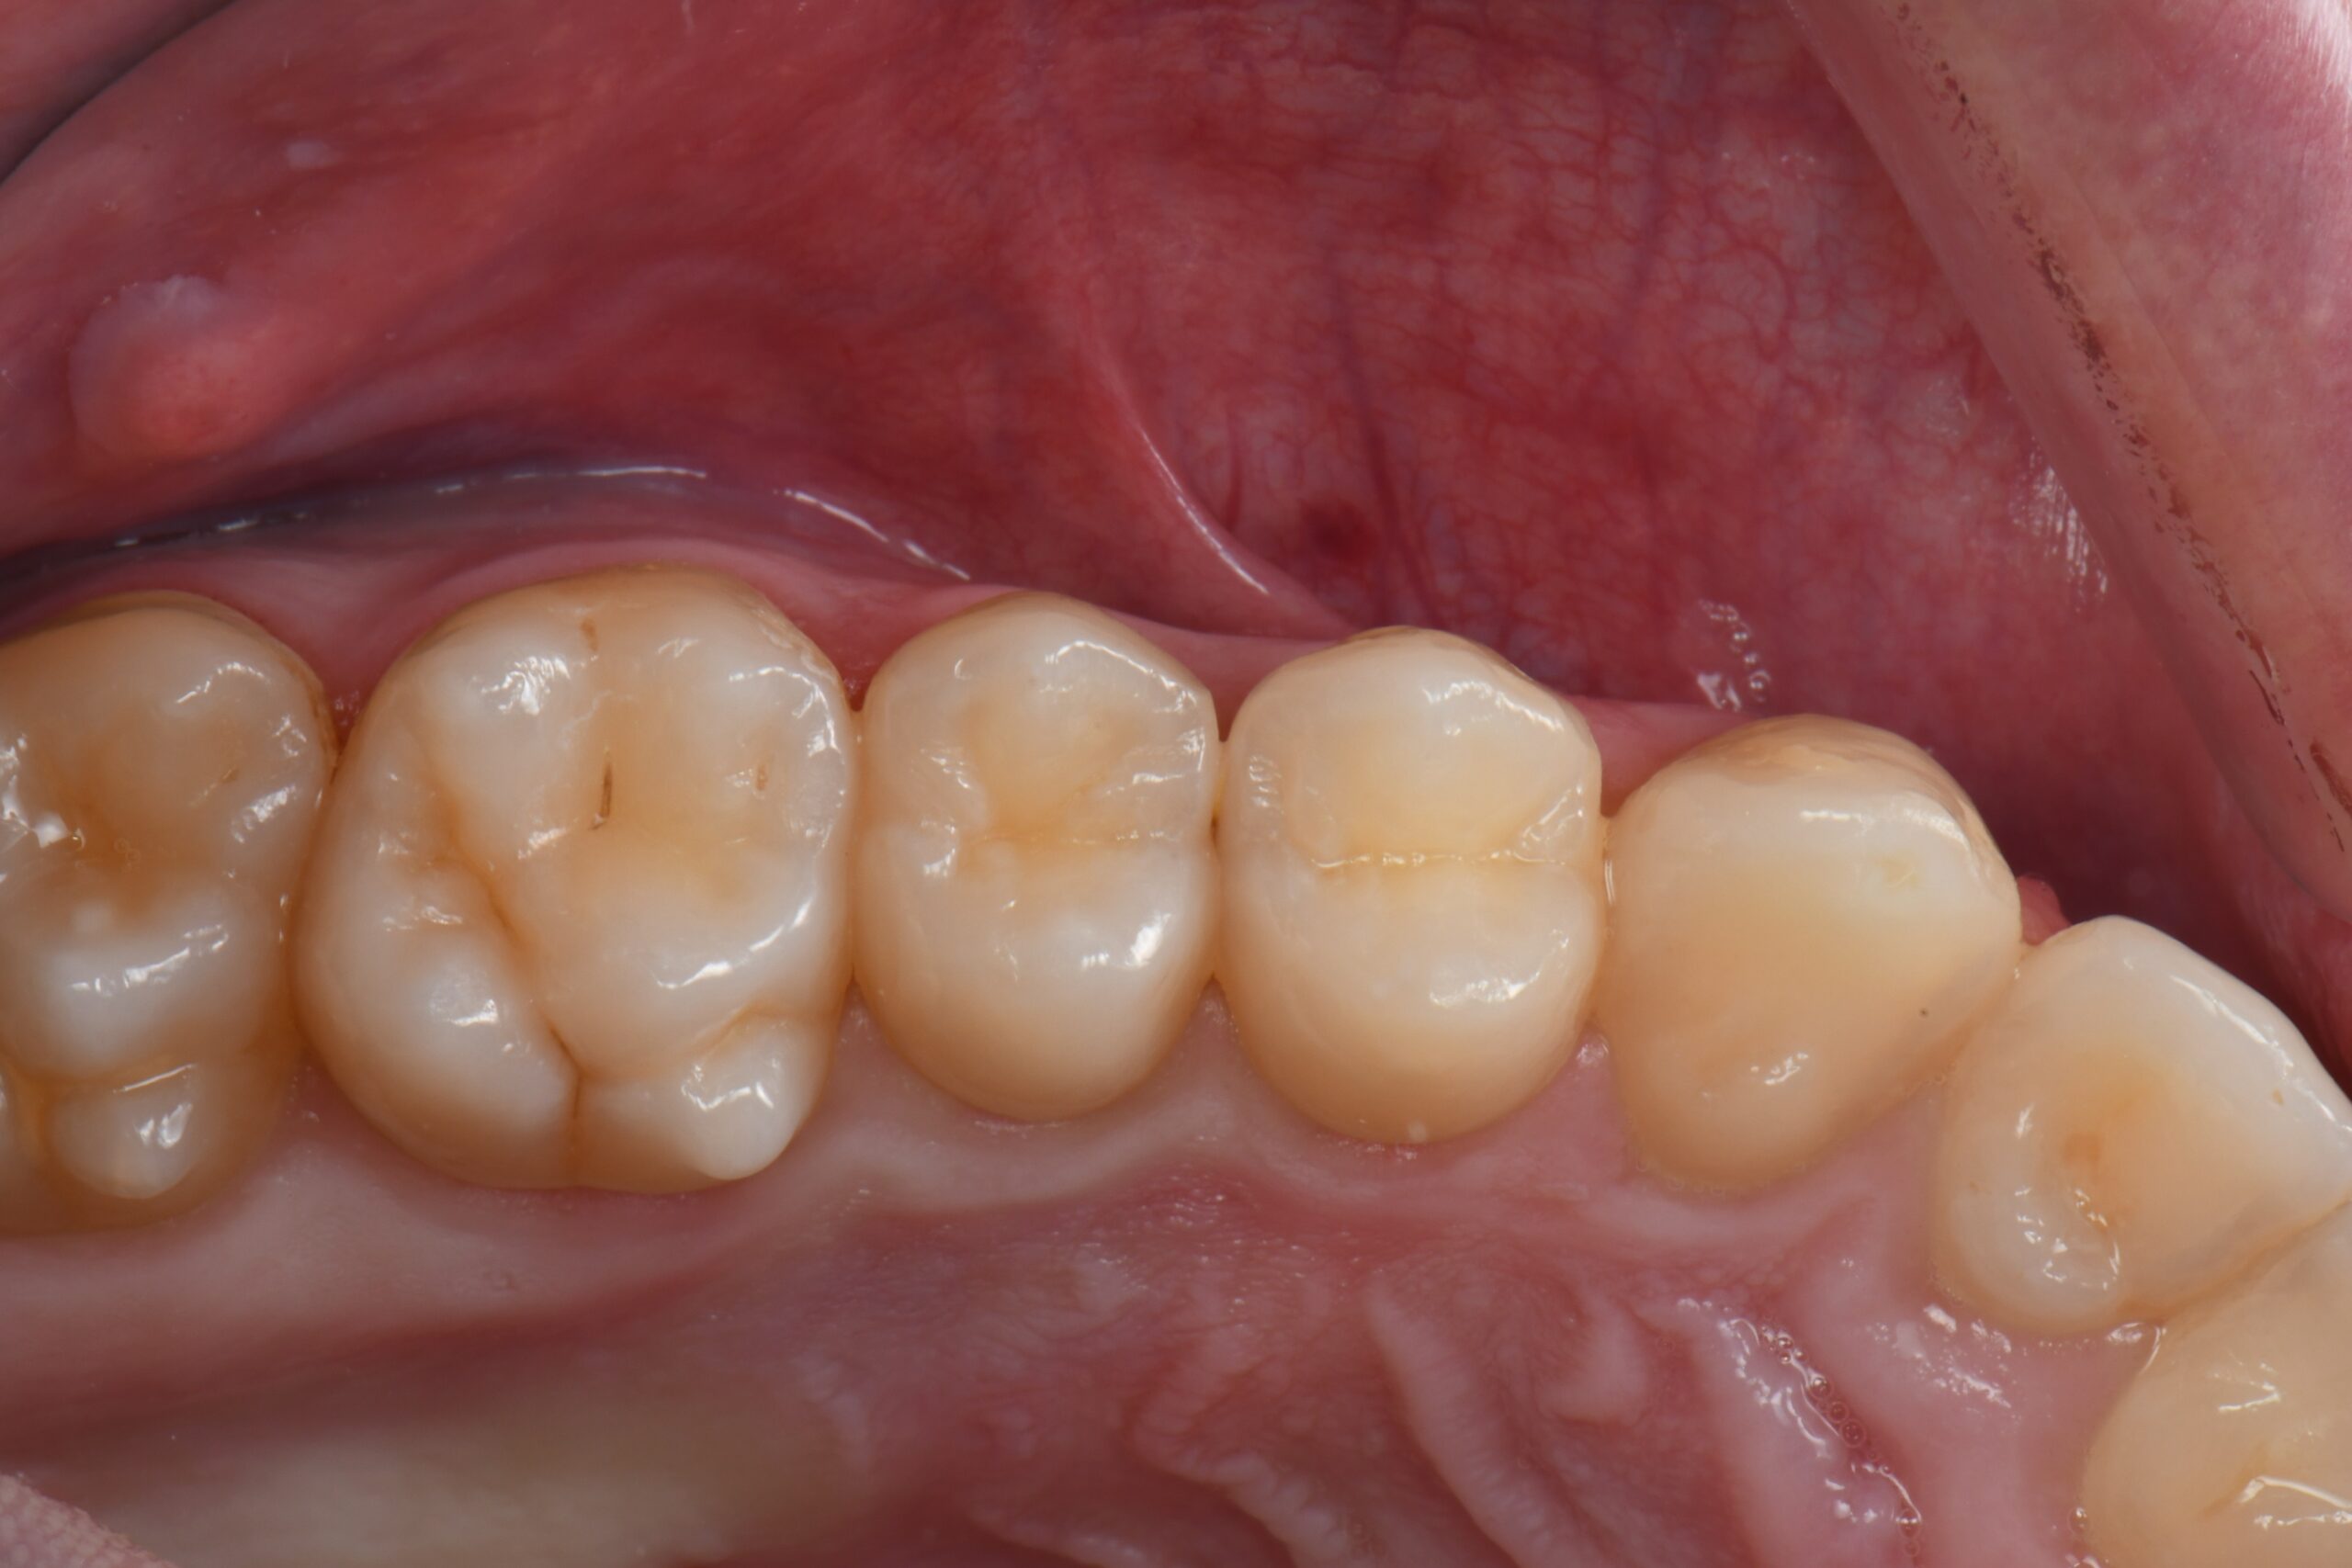

Close-up of upper teeth showing dental crowns and natural teeth with visible gums

Post-op vestibular view.